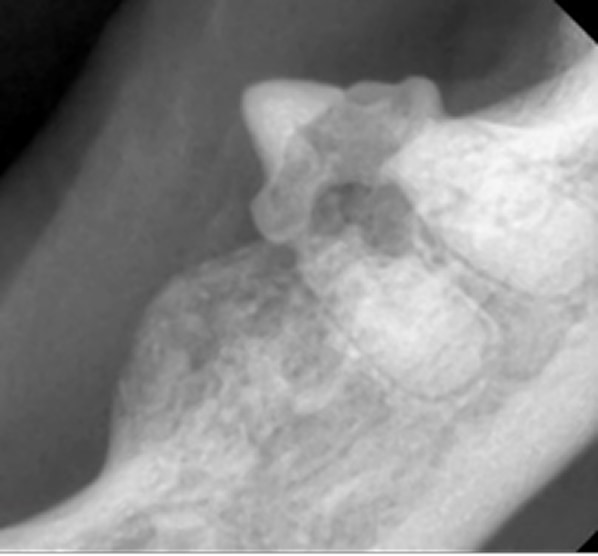

犬の歯周病は、口臭や歯のぐらつきなどから始まり、進行すると歯の痛みや脱落、全身疾患につながるリスクがあります。歯周病はプラークや歯石の蓄積によって引き起こされるもので、これが原因で歯周組織が徐々に破壊されていきます。早期の段階では、炎症や腫れを伴い、犬が口元を気にする仕草が見られることが多いです。しかし、口の痛みがあっても食欲が落ちにくいため、見過ごされやすいので注意が必要です。

治療は内科療法で症状を軽減することはできますが根治は難しく、根本的には全身麻酔下での歯石除去、歯周ポケットのクリーニング、抜歯が必要になることもあります。